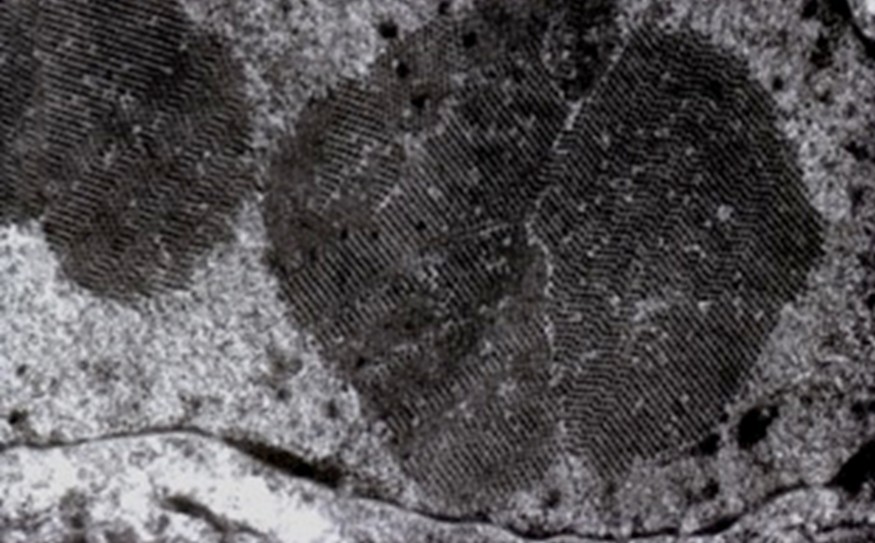

病理学的並びに分子病理学的手法を用いた疾患診断および病態解明

研究内容の特徴

帯広畜産大学が酪農・畜産地帯に位置することから、動物、特に産業動物の自然発生疾患に対する病理診断を日々行っています。その中から、新規あるいは稀有な病態を見出し、それら病態についての病理学的な研究を行うとともに、既知の病態の未解明の事象の解明に取り組んでいます。また、病理診断に分子生物学的手法を応用するための研究や、学内外の基礎・臨床研究分野の多くの先生と様々な共同研究も行っています。